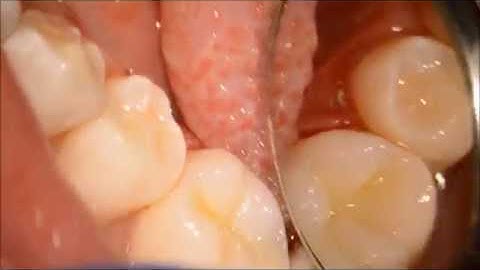

Direct cuspal coverage (overlay) after endodontic treatment